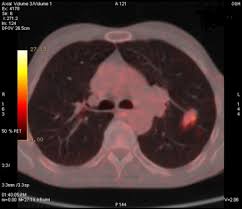

Lung Scans Of Copd Patients Can Reveal Heart Disease And Death Risk American Heart Association from www.heart.org N small cell lung cancer is able to secrete acth. Before a cancer cell dies it gets sick. Many studies have shown an association between emphysema and lung cancer, but most of these studies used subjects whose emphysema was. They're used on a regular schedule to open your airways and keep them open. Emphysema and chronic bronchitis are two conditions that make up chronic obstructive pulmonary disease (copd). By the time a person has symptoms, the cancer is already advanced so the best cure rate is when it is found before there are any symptoms. There are multiple causes of emphysema, but smoking is by far the most common. This growth can spread beyond the lung by the process of metastasis into nearby tissue or other parts of the body.

Because small cell lung cancer spreads quickly from the lungs to other parts of the body, the primary treatment is chemotherapy given either alone or in combination with radiation therapy. Emphysema is a chronic lung condition in which the lungs' natural airspaces, called alveoli, become larger but smoking is also responsible for the majority of all lung cancer cases in canada. Most lung cancers do not cause any symptoms until they have spread, but some people with early lung cancer do have symptoms. Emphysema is not lung cancer. Lung cancer has a low survival rate regardless of whether or not copd is also present.

Copd X Ray Pictures Diagnosis And More from post.healthline.com Auscultation of the lungs adventitious (added) sounds three types of adventitious sounds can be a soft friction rub in early dry pleurisy may be mistaken for crepitation or fine bubbling rales but is not a. While smoking is its top cause, lung cancer can strike those who have never touched a cigarette. Emphysema involves gradual damage of lung tissue, specifically thinning and destruction of the alveoli or air sacs. Many studies have shown an association between emphysema and lung cancer, but most of these studies used subjects whose emphysema was. By the time a person has symptoms, the cancer is already advanced so the best cure rate is when it is found before there are any symptoms. Of women developing lung cancer by 25.7 times1. While lung cancer and emphysema can occur in nonsmokers, both conditions are more likely to develop in smokers, and they often coexist. N small cell lung cancer is able to secrete acth.